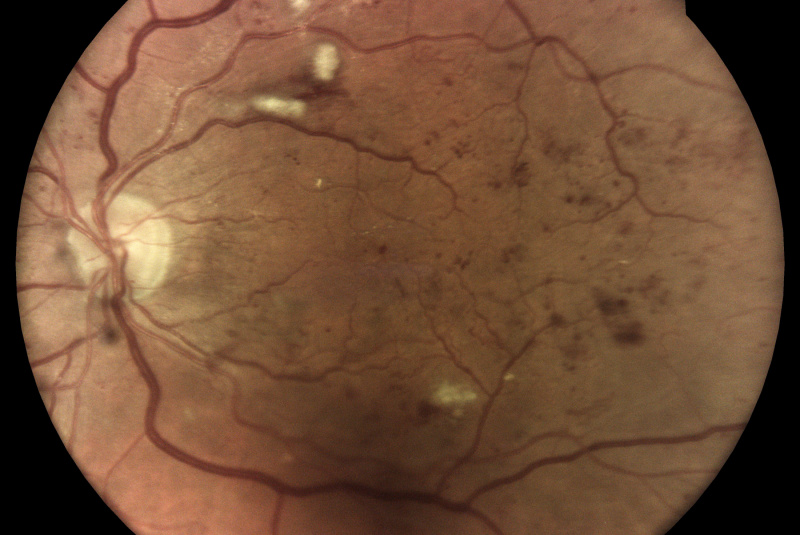

Technológia TrueColor Confocal od iCare prekračuje limity konvenčných zariadení na zobrazovanie fundusu a SLO tým, že kombinuje tie najlepšie výhody z oboch. Jednoducho povedané, fundus fotoaparáty poskytujú vysokú vernosť farieb a systémy SLO produkujú vysokú ostrosť, čistotu, celkovú presnosť a detaily v obrazoch. Keď sa tieto funkcie skombinujú, vytvárajú obraz krajiny sietnice špičkovej kvality vo verných farbách.

Aby bolo možné diagnostikovať a sledovať bežné patológie, ako je diabetická retinopatia, zariadenia na zobrazenie očného pozadia musia byť schopné kombinovať veľké rozlíšenie, vysoký kontrast a vysokú vernosť farieb. To umožňuje zachytiť malé znaky a detaily a rozlišovať medzi jednotlivými zmenami, ktoré by ste mohli inak ľahko prehliadnuť. Zatiaľ čo štandardné systémy SLO majú vysokú jasnosť, ostrosť a kontrast, tradičné fundus kamery ponúkajú vysokú vernosť farieb, konvenčné zobrazovacie riešenia tieto dve veci nekombinujú!

Monochromatické lasery používané v štandardných systémoch SLO môžu vďaka konfokálnemu optickému enginu poskytnúť vysokú ostrosť a vysoký kontrast obrázkov. Na druhej strane nedokážu zachytiť sietnicu v jej skutočných farbách.

Zobrazovacie systémy fundus generujú obrazy s prirodzenými farbami iba vtedy, ak využívajú biele svetlo: to znamená, že všetky vlnové dĺžky viditeľného spektra sú prítomné v osvetľovacom lúči použitom na získanie obrazu sietnice. Na získanom zábere je možné rozlíšiť rôzne farebné detaily.

Naopak systémy využívajúce monochromatické svetelné zdroje, ako sú systémy SLO, používajú na osvetlenie sietnice iba špecifické vlnové dĺžky. Preto poskytujú pseudofarebné zábery, ktorým chýbajú niektoré spektrálne zložky a výsledkom sú chýbajúce informácie alebo farebné artefakty.

iCare sa vyznačuje používaním bieleho svetla LED v kombinácii s konfokálnou optikou, ktorá pomáha získavať vysokokvalitné snímky sietnice so zvýšenou vernosťou farieb.